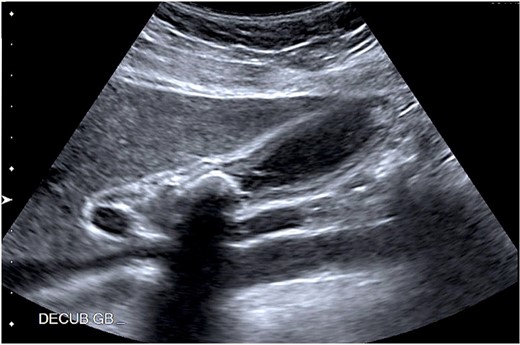

A 37-year-old female patient with a history of inflammatory bowel disease, gastroesophageal reflux disease, and a previous cesarean section was referred to the clinic for recurrent episodes of biliary colic. Her symptoms included right upper quadrant pain, along with nausea and vomiting. An abdominal ultrasound revealed a 2.1 cm gallstone in the GB neck and wall thickening. There was no dilation of the biliary tree, and the pancreas appeared normal (Fig. 1). Laboratory results did not show abnormalities, and the physical examination was unremarkable.

Abdominal ultrasound showing a 2.1 cm calcified gallstone in the gallbladder neck, and a thickened wall.